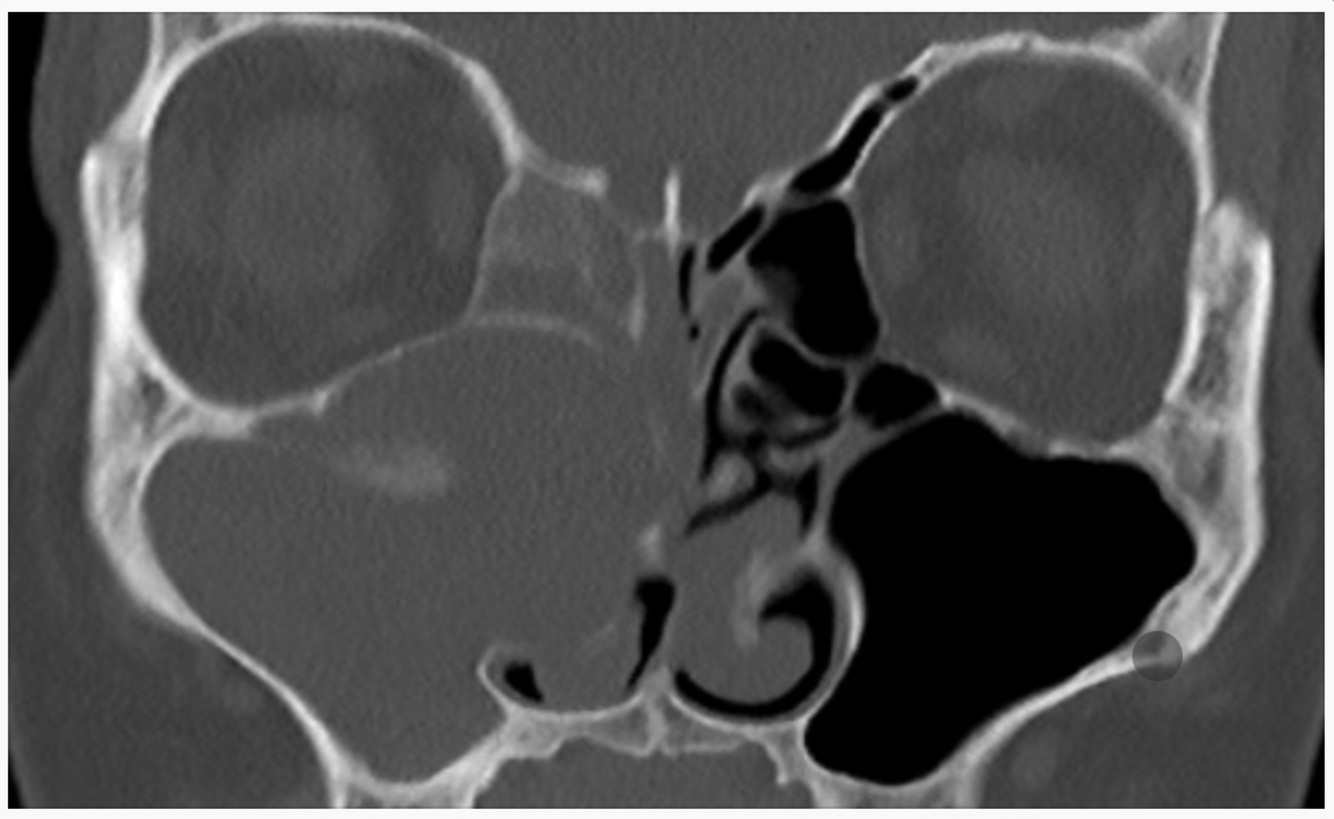

A 28-year-old man from Sudan presents with nasal obstruction secondary to a 9 year history of painless nasal mass (CT shown below). Biopsy of the left nasal mass shows histiocytes with “foamy, moth-eaten” cytoplasm with epithelioid cells. Silver stain showed intracellular bacilli. What is the most likely diagnosis?

A

Rhinoscleroma.

(Rhinoscleroma is caused by infection with Klebsiella rhinoscleromatis. Sporadic cases have been reported in the United States, but the disease is endemic in Central and South America, Africa, the Middle East, and parts of Asia. Disease progression moves through exudative, granulomatous, and sclerotic phases. The pathologic appearance described here is characteristic of the granulomatous phase.)